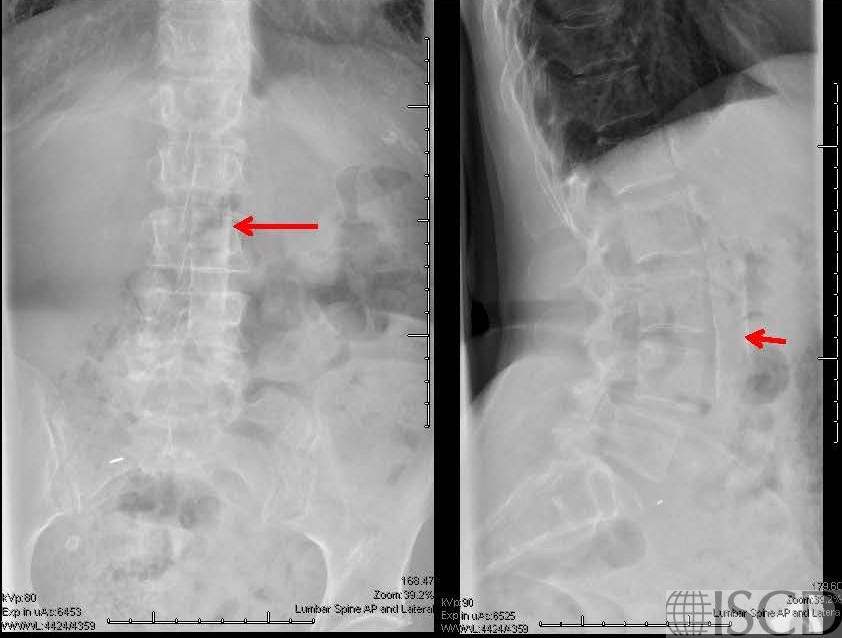

The accompany radiographs also show the aortic calcification.

This DXA scan shows aortic calcification, with the accompanying postero-anterior and lateral radiographs showing the aortic calcification. The red lines are point to the aortic calcification. Aortic calcification will tend to overestimate bone mineral density. Aortic calcification is easily appreciated on vertebral fracture assessment (VFA) images. The effect of aortic calcification on bone mineral density has been found to be variable in the literature, however, any authors have found that the additional calcium can increase lumbar spine BMD.